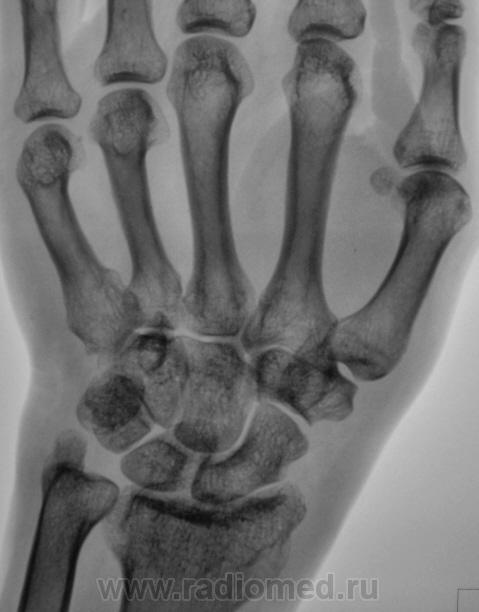

Пол пациента: Женский пол Тип патологии: Другое Область исследования: Скелетно-мышечная система Методы исследования: Rg Пациент с диагнозом "ревматоидный артрит" направлен на рентгенографию кистей. https://radiomed.ru/sites/default/files/styles/case_slider_image/public/user/12/2.pb100037a.jpg?itok=yFjpd1IX https://radiomed.ru/sites/default/files/styles/case_slider_image/public/user/12/3.pb100038.jpg?itok=92itQ56R https://radiomed.ru/sites/default/files/styles/case_slider_image/public/user/12/4.pb100038a.jpg?itok=rsA7mSo8 ID:8677 Чт, 11/11/2010 - 01:03 #1 Makcimalist Не на сайте Был на сайте: 11 лет 8 месяцев назад Зарегистрирован: 08.05.2010 - 14:28 Публикации: 1994 - специфич. признаков начальных стадий РА не нашёл... -------------- "Просто, по видимости, не видеть логики в очевидных вещах - это тоже одно из свойств некоторых умов, наряду с грустными думами о свойствах ума других." © Vega 08/10/2011 Чт, 11/11/2010 - 14:44 #2 Катенёв Валенти... Не на сайте Был на сайте: 7 лет 2 недели назад Зарегистрирован: 22.03.2008 - 22:15 Публикации: 54876 Норму писать? Сб, 13/11/2010 - 01:28 #3 Makcimalist Не на сайте Был на сайте: 11 лет 8 месяцев назад Зарегистрирован: 08.05.2010 - 14:28 Публикации: 1994 Начальные проявления остеоартроза пястно-фаланговых,м/фаланговых суставов... (Норма бывает п/е рождения... и то не всегда...) -------------- "Просто, по видимости, не видеть логики в очевидных вещах - это тоже одно из свойств некоторых умов, наряду с грустными думами о свойствах ума других." © Vega 08/10/2011 Сб, 13/11/2010 - 19:53 #4 Глазков Игорь А... Не на сайте Был на сайте: 9 месяцев 2 недели назад Зарегистрирован: 19.12.2008 - 20:41 Публикации: 1597 Имеются кистовидные просветления костной ткани в эпифизах костей. Прийди к Себе

- специфич. признаков начальных стадий РА не нашёл...

Начальные проявления остеоартроза пястно-фаланговых,м/фаланговых суставов...

Имеются кистовидные просветления костной ткани в эпифизах костей.